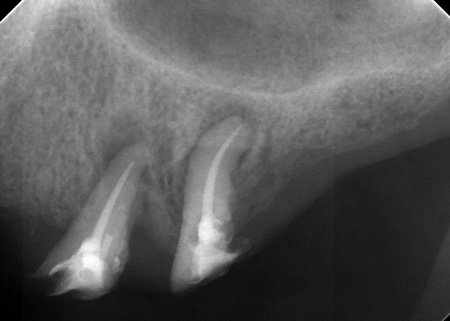

まず、上顎の状態や残存歯について詳しく検査し、温存が難しいと判断した左上の歯3本(犬歯、第1小臼歯、第2小臼歯)を抜きました。

抜歯後は、即時インプラント埋入手術を実施しています。